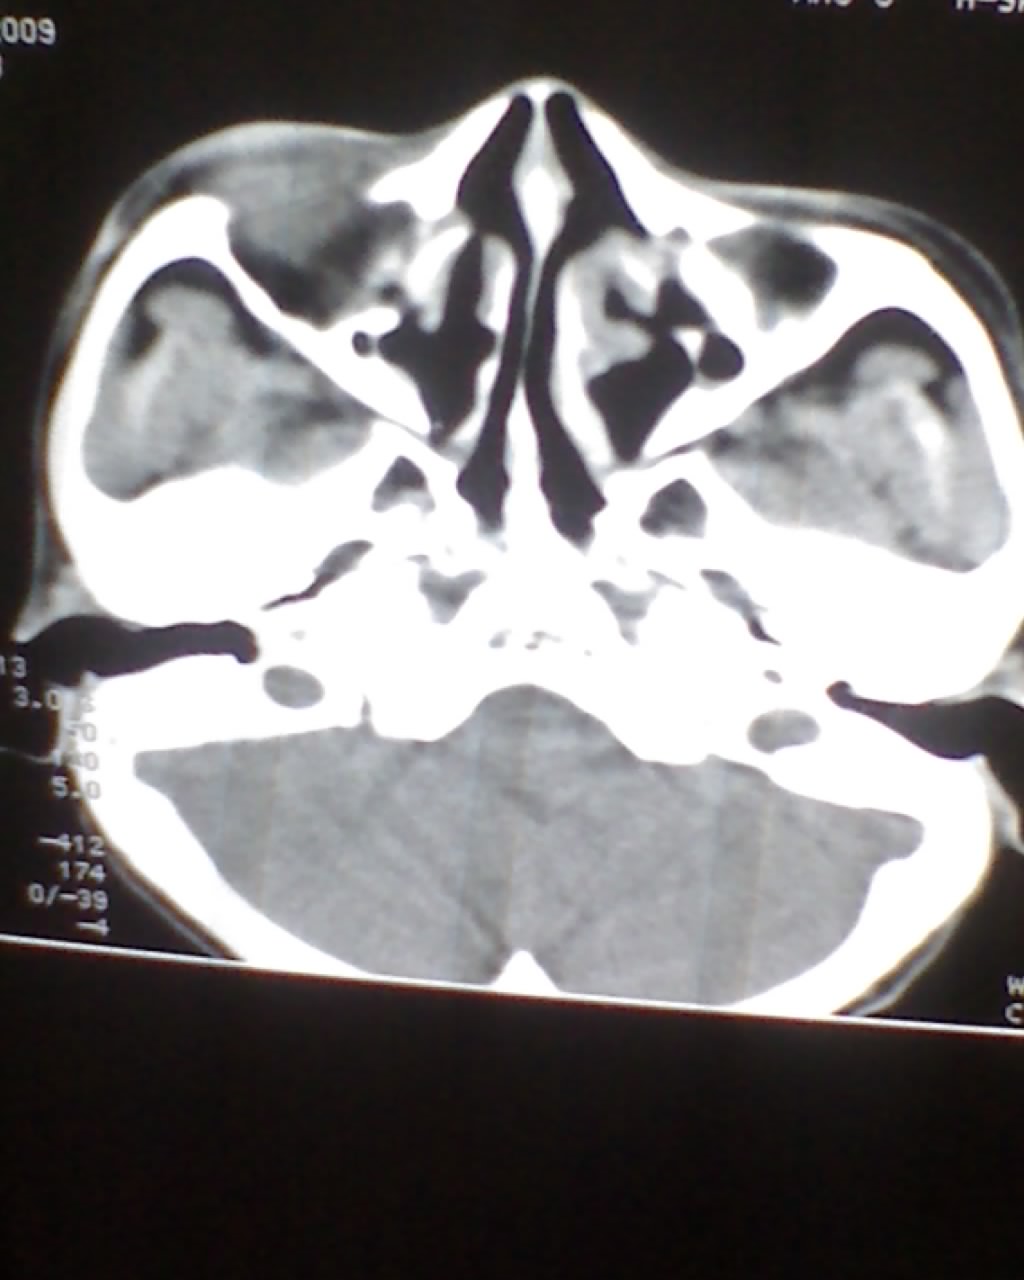

女,45岁,右眼突出,视力模糊来诊。

1)不排除嗅神经母细胞瘤侵犯双侧眼眶可能。2)双侧额窦及双侧蝶窦炎症。

双侧筛窦可见软组织影充填,筛板破坏,肿块突向双侧眼眶内,以右侧为明显,右侧眼球向前外推压,右视神经稍外移。

双侧额窦,筛窦可见软组织影充填,筛板破坏,肿块突向双侧眼眶内,以右侧为明显,右侧眼球向前外推压,右视神经稍外移。

考虑良性病变,黏液囊肿可能性大,不除外内翻乳头状瘤等,建议强化.前者不增强.